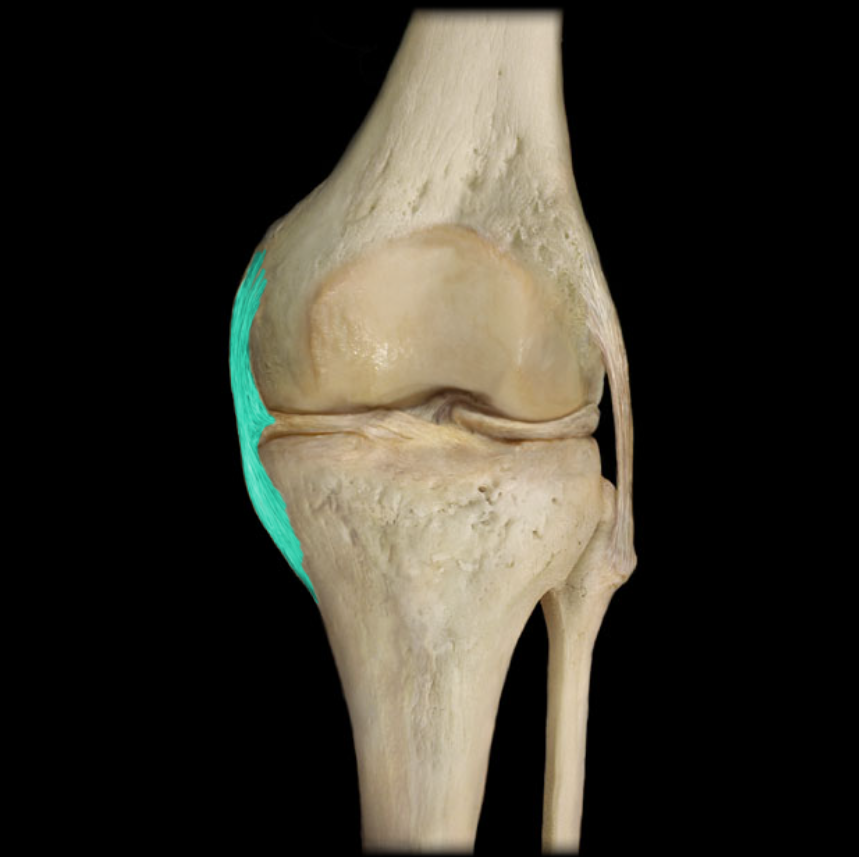

Tibial collateral ligament